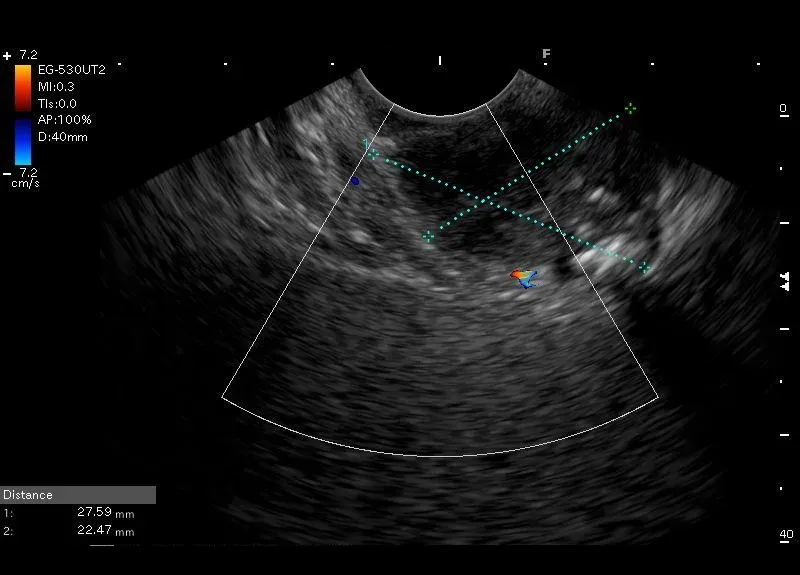

Widoczna w ścianie żołądka, owalna, heterogenna zmiana wielkości około 28/25 mm, zawierająca hiperechogeniczne  odbicia z cieniem akustycznym (mogące odpowiadać zwapnieniom)-obraz może odpowiadać trzustce ektopowej  w żołądku